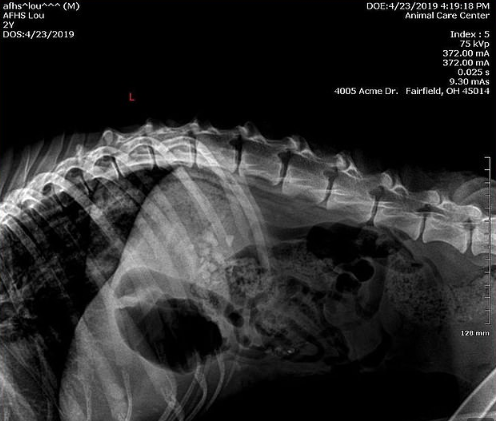

The X-ray images of Lou showed that it had rocks in its digestive system. Richard Jones, Butler County Sheriff said that no human being with a sane mind could look at Lou and think it was acceptable.